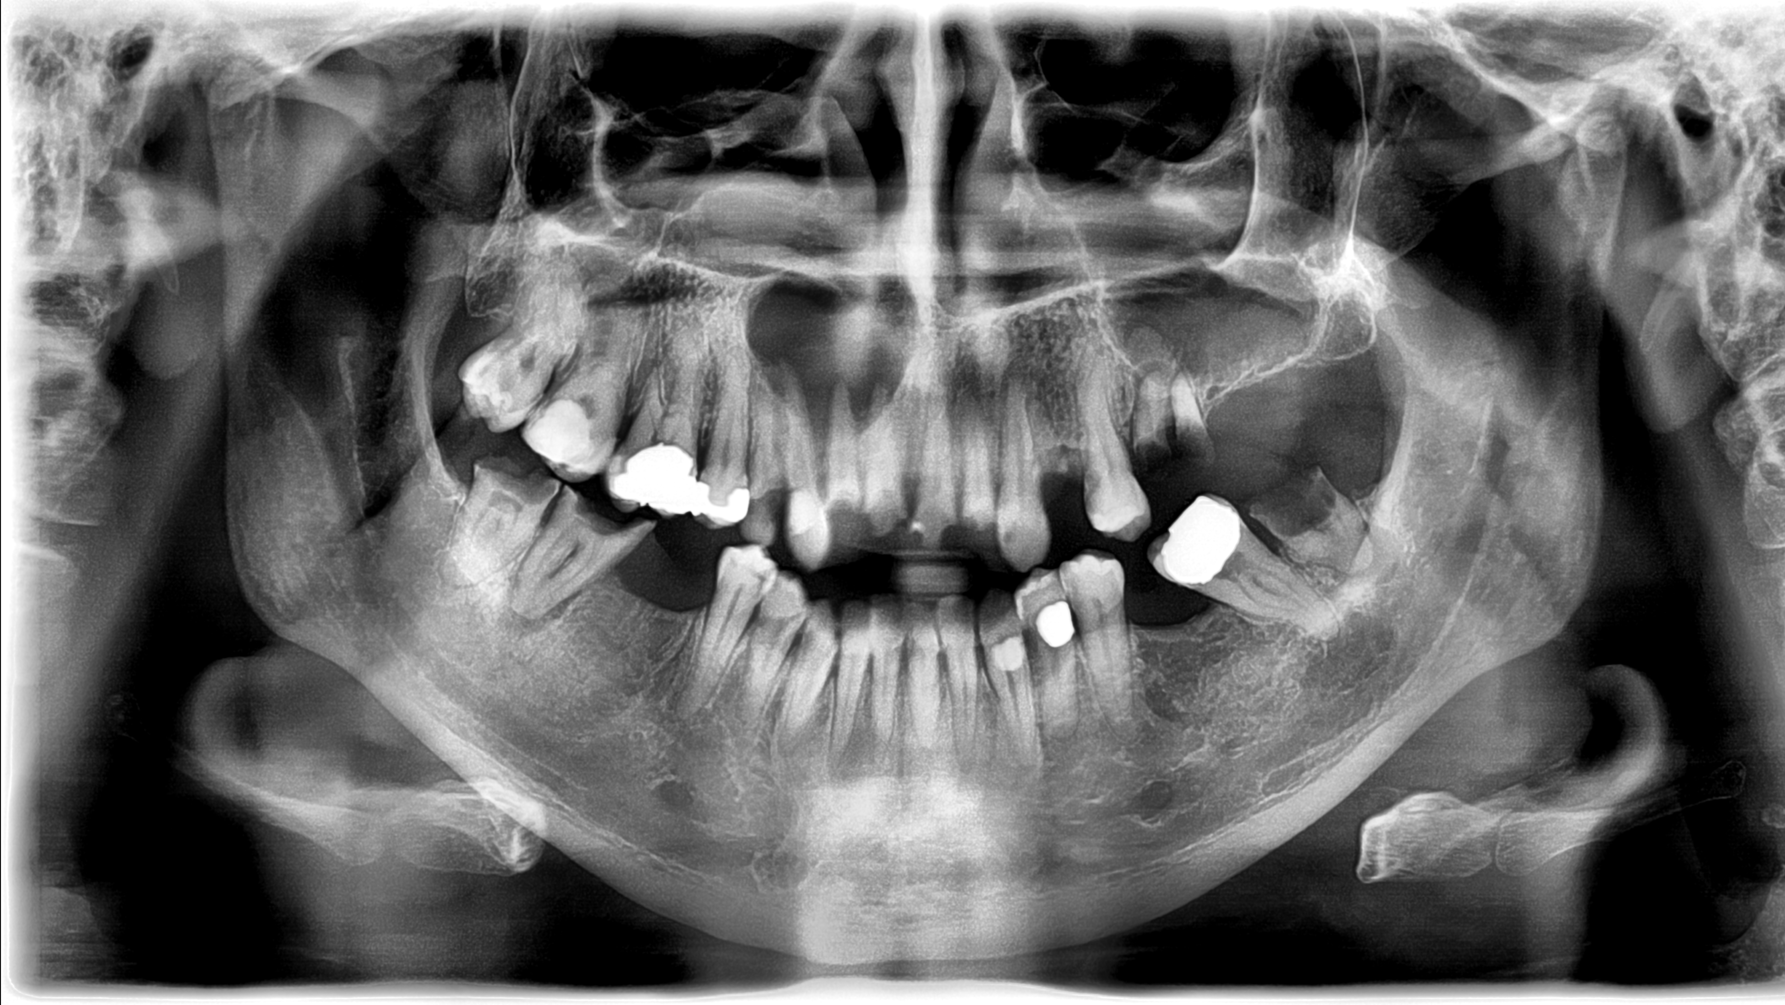

A limited exam reveals rampant decay. The panoramic radiograph shows badly decayed teeth on the lower right side, with an apical radiolucency and associated swelling in the buccal vestibule. Also noted is a well-defined radiolucency above the apexes of tooth nos. 5–9. There is some expansion around the bone; the lesion is not fluctuant or mobile. Nos. 5–9 are severely decayed.

Radiographically, these lesions have well-defined borders with an oval/round radiolucency.1 If the lesion is large enough, the roots of adjacent teeth can be displaced; jaw fracture is a possibility if the lesion is large enough and in the right location.